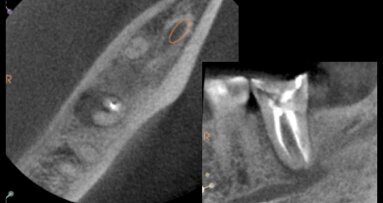

La Dra. Clara Adrada, Especialista en Endodoncia que ejerce en Popayán, Colombia, es la creadora de la técnica Reimplante Intencional Digital (R.I.D).